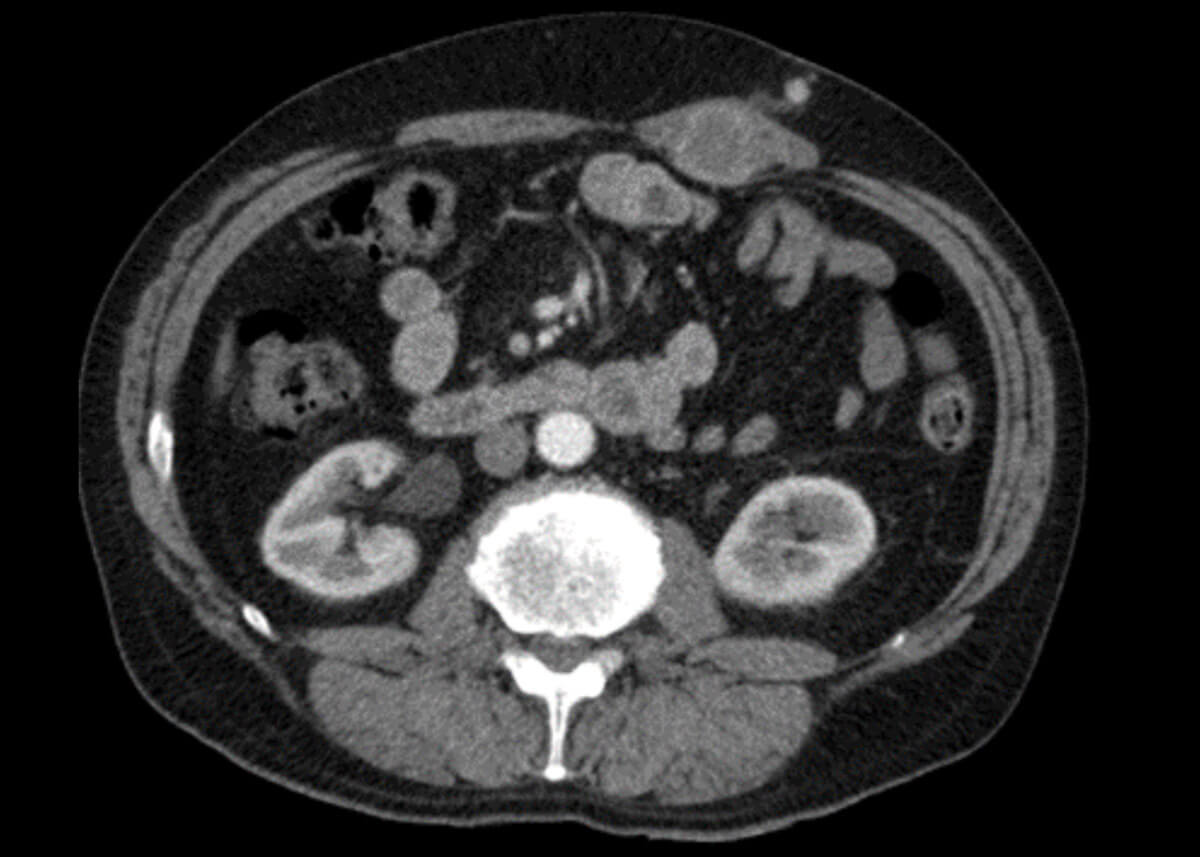

Figure 2: An axial CT image 12 months post surgery demonstrating a thickening of the left rectus muscle.

A surveillance CT scan was performed one year later demonstrating several small longstanding inflammatory lung nodules, and a thickening of the left rectus muscle around the location of the previous port site (Figure 2). This was reported as likely post-surgical change. On review, the patient complained of some pain in the region, and was managed at the time with topical diclofenac cream with a plan for repeat imaging in six months.